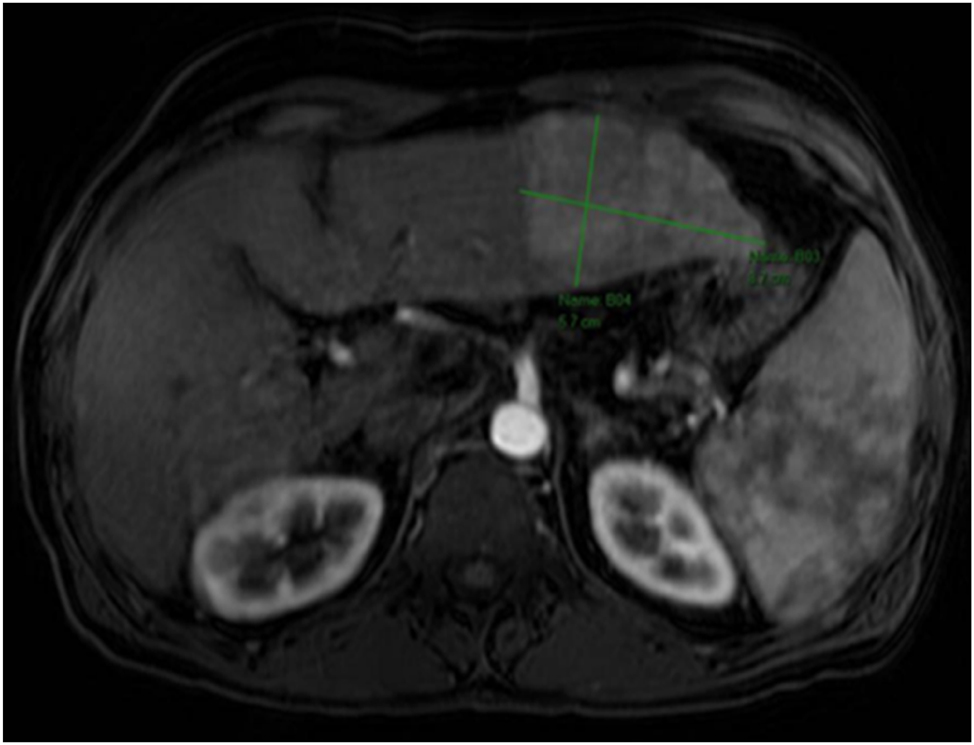

Requires Authentication UnlicensedMultiple hepatic sclerosing hemangiomas mimicking malignant lesions, a diagnostic dilemma: case report and literature reviewLicensedOctober 7, 2025